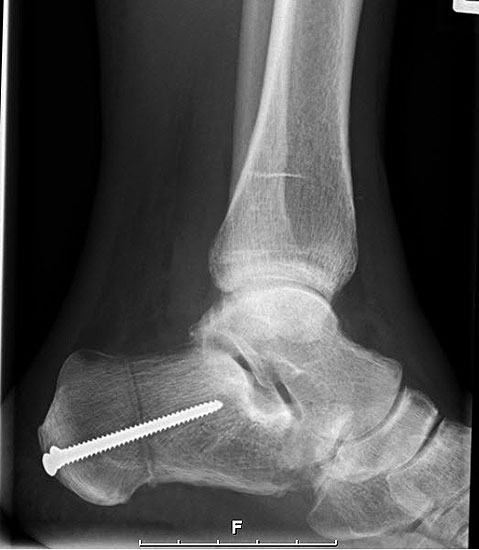

Stadium IV – komplette Rückfuß-Arthrodesen

- TTC- / pantalare Arthrodese

Im Stadium IV der (fixierten) Planovalgus Deformität und lateral betonter OSG-Arthrose umfaßt die operative Therapie eine korrigierende Arthrodese von OSG und USG-Arthrodese (Tibio-talo-calcanear = TTC Fusion) oder bei Arthrose in der Chopart-Gelenkreihe eine pantalare Arthrodese 5556.

Für die TTC-Arthrodese haben sich retrograde Rückfußnägel bewährt, da sie eine gute Primärstabilität bieten und vergleichsweise wenig Weichteildissektion erfordern. Die Indikation muss aber sehr differenziert gestellt werden, zumal das Gangbild anschließend erheblich eingeschränkt sein wird und Anschlußarthrosen trotz optimaler Schuhversorgung mit Abrollrampe zu erwarten sind. Solange die OSG-Arthrose beschwerdearm bleibt, sollte daher auch eine umfangreiche Korrektur der Planovalgus-Deformität mit Rekonstruktion des Ligamentum deltoideum anstelle der TTC- und pantalaren Arthrodese favorisiert werden 57.